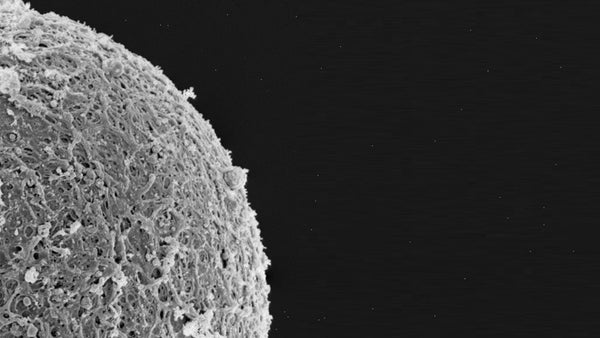

Session 151: Reproductive BioMedicine in Space III offered a deep and wide-ranging exploration of how human reproduction may be affected by life beyond Earth. As our ambitions turn toward Mars and commercial spaceflight becomes a reality, understanding how space environments influence reproductive health is becoming increasingly urgent. This session gathered leading voices in reproductive science, space medicine, urology, genomics, and ethics to examine both the opportunities and challenges of conceiving, maintaining fertility, and safeguarding reproductive health in space.

A key voice in the session was Dr. Begum Mathyk, a NASA-trained physician and ObGyn specializing in reproductive endocrinology and space medicine. Currently completing a fellowship at the University of South Florida, Dr. Mathyk has held academic positions in both Türkiye and the U.S. and serves as Associate Co-Chair of SREI. She made history by performing the first gynecologic ultrasound in weightlessness and plays an active role in international space health initiatives. Her talk provided valuable insights into how space environments could impact female reproductive health, highlighting both the gaps in knowledge and the need for innovation in women’s health research, both on Earth and in orbit.

Dr. Jeffrey A. Jones, Professor at Baylor College of Medicine and former NASA Flight Surgeon, together with Dr. Blair T. Stocks, Assistant Professor in Male Reproductive Medicine at Baylor, presented findings on the male reproductive system in space. They explored the effects of microgravity and radiation on male fertility, offering a blend of laboratory research and clinical implications relevant to future space missions.